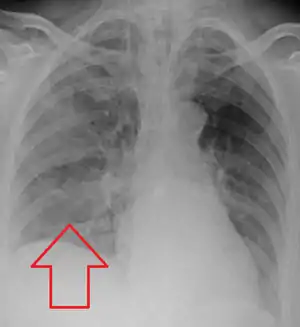

.jpg.webp)

Evaluation of aspiration is generally performed with a video fluoroscopic swallowing study involving radiologic evaluation of the swallowing mechanism via challenges with liquid and solid food consistencies. These studies allow for evaluation of penetration to the vocal folds and below but are not a sensitive and specific marker for aspiration.[15] Additionally, it is difficult to distinguish between aspiration pneumonia and aspiration pneumonitis.[16]

Aspiration pneumonia is typically diagnosed by a combination of clinical circumstances (people with risk factors for aspiration) and radiologic findings (an infiltrate in the proper location).[2] A chest x-ray is typically performed in cases where any pneumonia is suspected, including aspiration pneumonia.[17] Findings on chest x-ray supportive of aspiration pneumonia include localized consolidation depending on the patient's position when the aspiration occurred.[18] For example, people that are supine when they aspirate often develop consolidation in the right lower lobe of the lung.[18] Sputum cultures are not used for diagnosing aspiration pneumonia because of the high risk of contamination.[19] Clinical symptoms may also increase suspicion of aspiration pneumonia, including new difficulty breathing and fever after an aspiration event.[6] Likewise, physical exam findings such as altered breath sounds heard in the affected lung fields may also be suggestive of aspiration pneumonia.[6] Some cases of aspiration pneumonia are caused by aspiration of food particles or other particulate substances like pill fragments; these can be diagnosed by pathologists on lung biopsy specimens.[20]